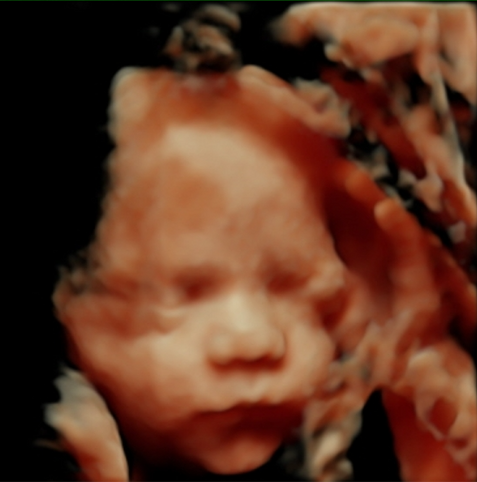

We offer elective 2D/3D/4D/5D pregnancy ultrasounds designed to create a calm, memorable experience for expecting families. These non-diagnostic scans allow you to bond with your baby and capture special moments in a comfortable, welcoming setting.

Gallery